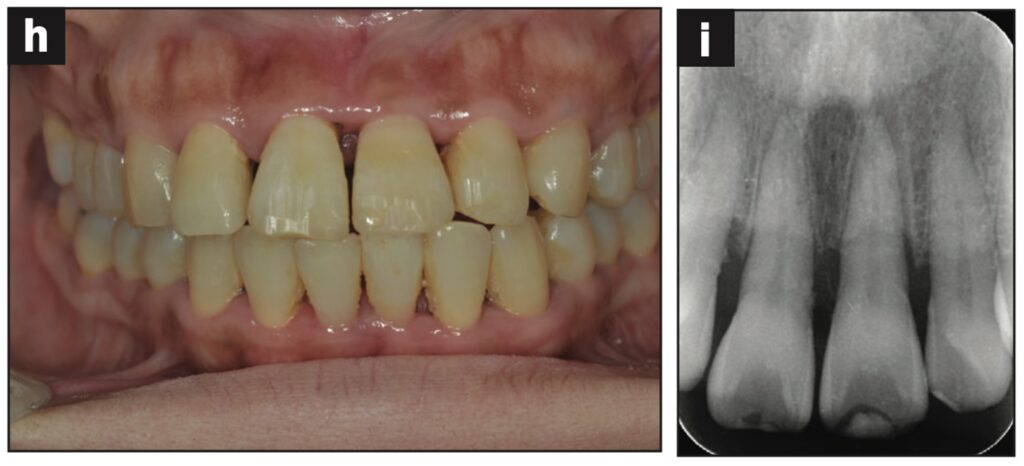

Bệnh nhân nữ 24 tuổi bị ngã khiến răng cửa giữa hàm trên bên trái bị lệch sang một bên. Sáng hôm sau, bệnh nhân đến phòng khám, được cố định bằng composite quang trùng hợp và lấy dấu.

Sáu tiếng sau, bệnh nhân quay lại và nhận hàm duy trì.

Bệnh nhân được hướng dẫn đeo hàm duy trì cả ngày trừ khi đánh răng. Các thử nghiệm độ sống tủy được thực hiện sau 1, 7, 14 và 21 ngày. Kiểm tra độ lung lay răng, gõ, sờ, thử tủy EPT và chụp X quang sau 28 ngày. Răng có độ lung lay +1 theo chiều ngoài trong và không có đáp ứng với thử nghiệm tủy EPT.

Ba tháng sau, răng đã được trám phục hồi và đáp ứng EPT (8/10). Tại thời điểm tái khám sau 4 tháng, răng đáp ứng với EPT (4/10). Sau 5 tháng, ghi nhận có lỗ dò. Răng không đáp ứng với EPT. Tổn thương quanh chóp được nhìn thấy trên X quang.

Răng được chẩn đoán là hoại tử tủy và điều trị tủy được thực hiện trong 2 lần hẹn. Một tháng sau (6 tháng sau khi chấn thương xảy ra), lỗ dò biến mất và chụp X quang cho thấy quá trình lành thương (hình 2).